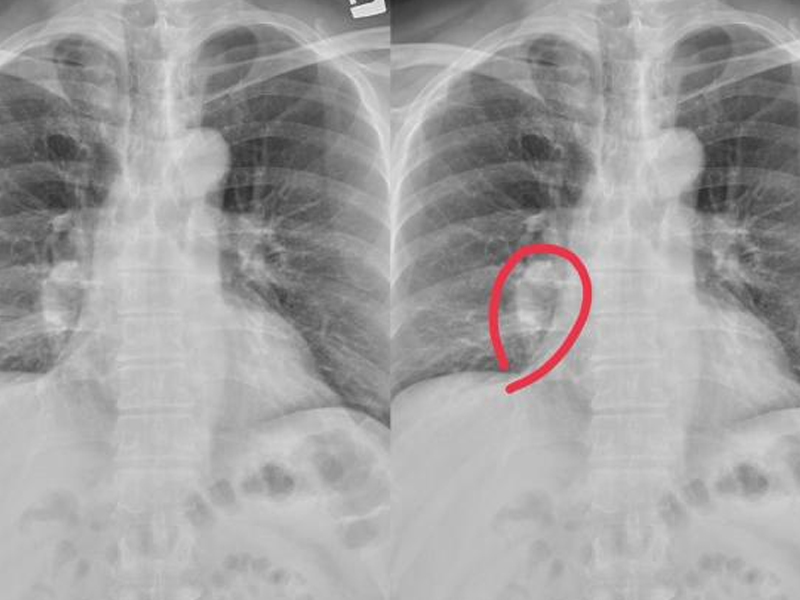

有種癌,一發現就是晚期